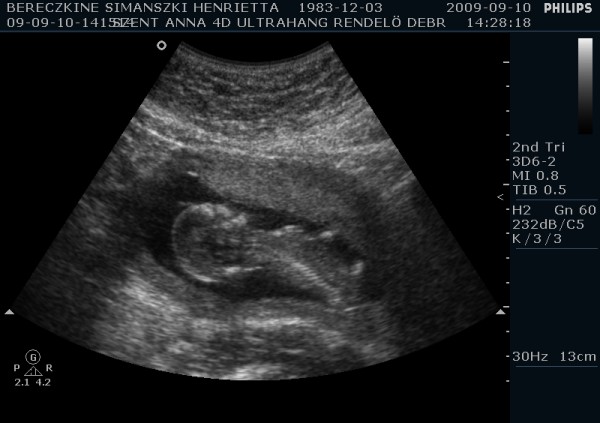

Megjöttem én is ismét, tettem fel képeket. A párom ragaszkodott hozzá, hogy kérjünk DVD-t, így hát átkapcsoltak 4D-be is. Kb. 10-15 perc lett a dvd, nagyon jópofa, látszik mindene. Mozognom, köhögnöm kellett nekem is, hogy a baba felébredjen, de amikor ébren volt, hihetetlen mit művelt. Egyik helyről a másikra átment, az első képen épp ez látható. :-) Ott a lábai vannak alul, a térdei nagyon jól látszanak. Épp ekkor rúgta át magát egy neki kényelmesebb pozícióba. :-)

A második képet meg csak azért tettem fel, hogy ez is legyen, de majd próbálok még a filmből kiszedni jobb képeket. Ezeket a párom csinálta 2 perc alatt.